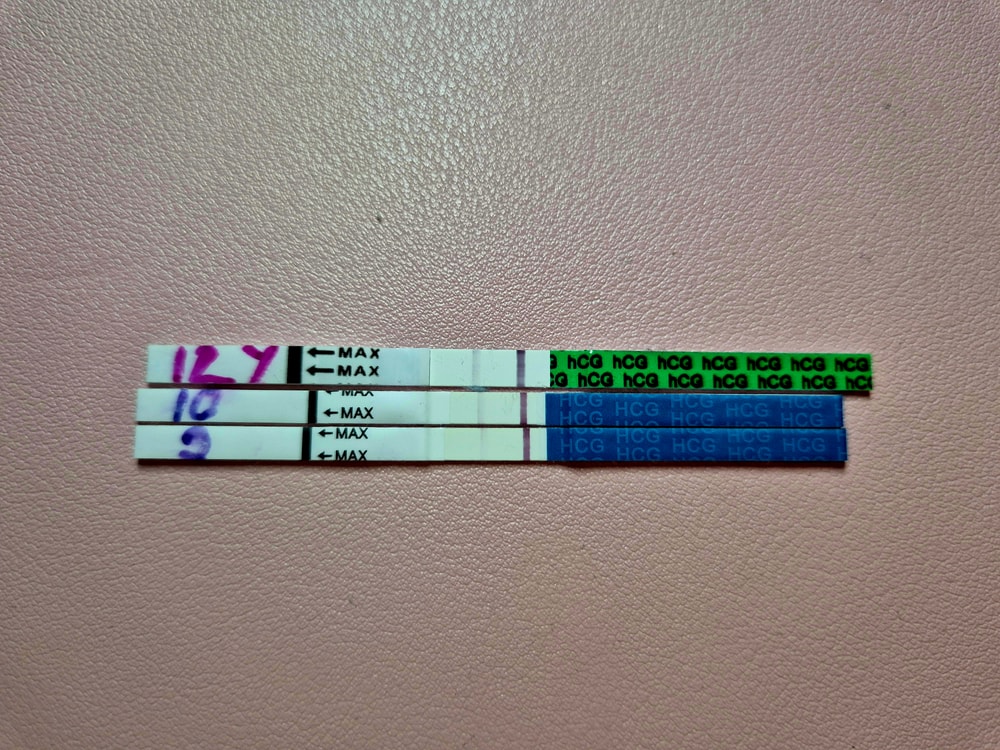

Вчера пришёл хороший хгч, сегодня решила утром сделать еще раз тест, был только answer 10мме, но что то полоска бледная и переживания накрыли

А утром такой бледный тест( у всех он уже почти как контрольная...

Скажите, это норма или может тесты такие... уже незнаю что думать